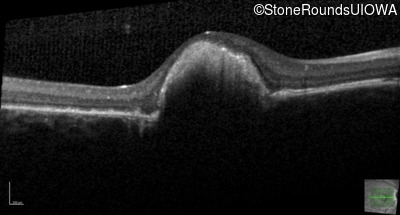

Optical Coherence Tomography - Right - 20/100 +1 sc

Exemplar / OCT Stack

Optical Coherence Tomography - Left - 20/20 sc